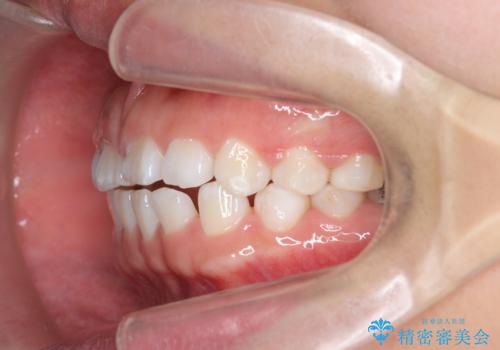

インビザライン 気になるすきっ歯の改善

- 上下顎前歯部の空隙が気になるので治したいと当院にいらっしゃった方の症例です。

非抜歯、インビザラインによる矯正治療により歯と歯の隙間および前歯の上下の隙間を閉じ切りました。